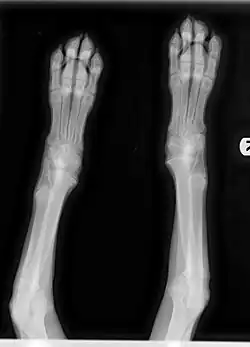

Figure 3: X-Ray image of HOD presentation in 4-month-old Weimaraner puppy. Note "moth-eaten" appearance of metaphyses.

Diagnosis relies on clinical signs and characteristic changes in radiographic images of the metaphyses. Bone changes can be observed on radiograph, and the disorder may progress to actual angular limb deformity. In the early stage of the illness, the metaphyseal area on X-ray may be observed to have an uneven radiolucent zone parallel to the physis with a thin band of increased radiodensity directly bordering the physis. Early stage radiographic changes have sometimes been described as having a "moth-eaten" appearance (see Figure 3). As the disease progresses, the radiolucent line may disappear and radiodensity may increase in the affected area as the body attempts to repair damage. Relapses can cause new radiolucent lines. This area is often followed by a dark line at the metaphysis, which may progress to new bone growth on the outside of that area. This area represents microfractures in the metaphysis and bone proliferation to bridge the defect in the periosteum.[7]